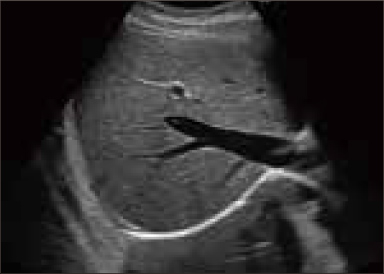

OFF

ON